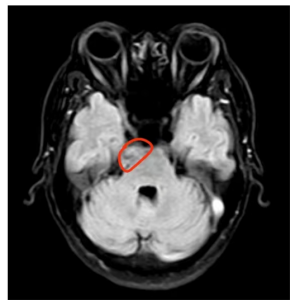

影像阅片时,樊天禹告诉患者,他的颅内肿瘤位于右侧桥小脑角区,该位置位于脑干及小脑之间,有重要的血管、颅神经,肿瘤的大小约有2cm,治疗方法建议手术切除。

核磁共振影像结果显示颅内肿瘤